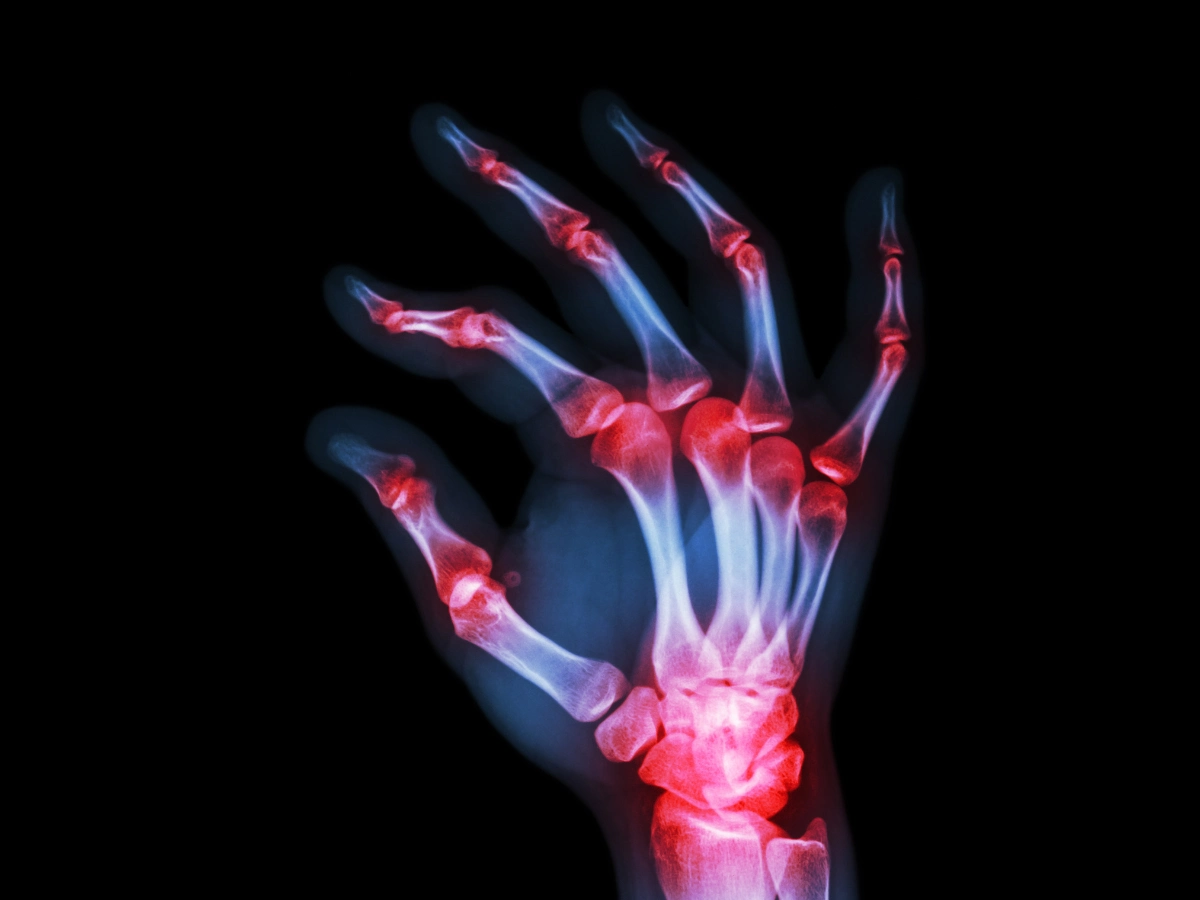

손가락 관절염 증상 및 치료법

손가락 관절염은 손가락 관절 부분에 관절염이 발생한 것으로, 손가락을 움직일 때 운동 제한과 통증이 발생하기도 합니다.

특히 손가락 관절은 자주 사용하는 부위이며 다른 관절보다 약한 부위인 만큼, 손가락 관절염 증상을 방치할 경우 일상생활에 큰 불편함을 느끼게 될 수 있고 심지어는 손가락 모양의 변형을 초래할 수 있습니다.